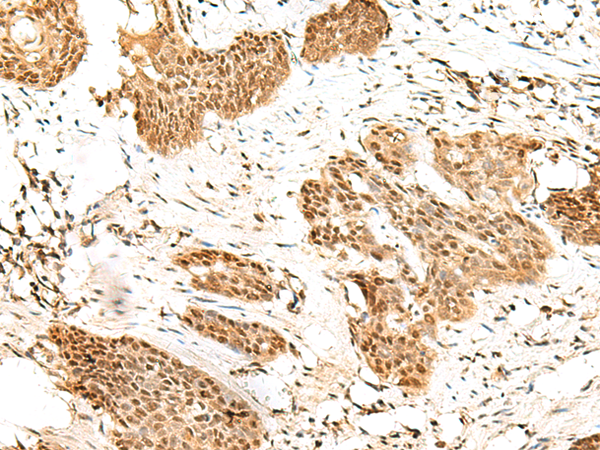

ELISA, IHC

IHC positive control:

Human thyroid cancer and Human cervical cancer

IHC Recommend dilution:

30-150